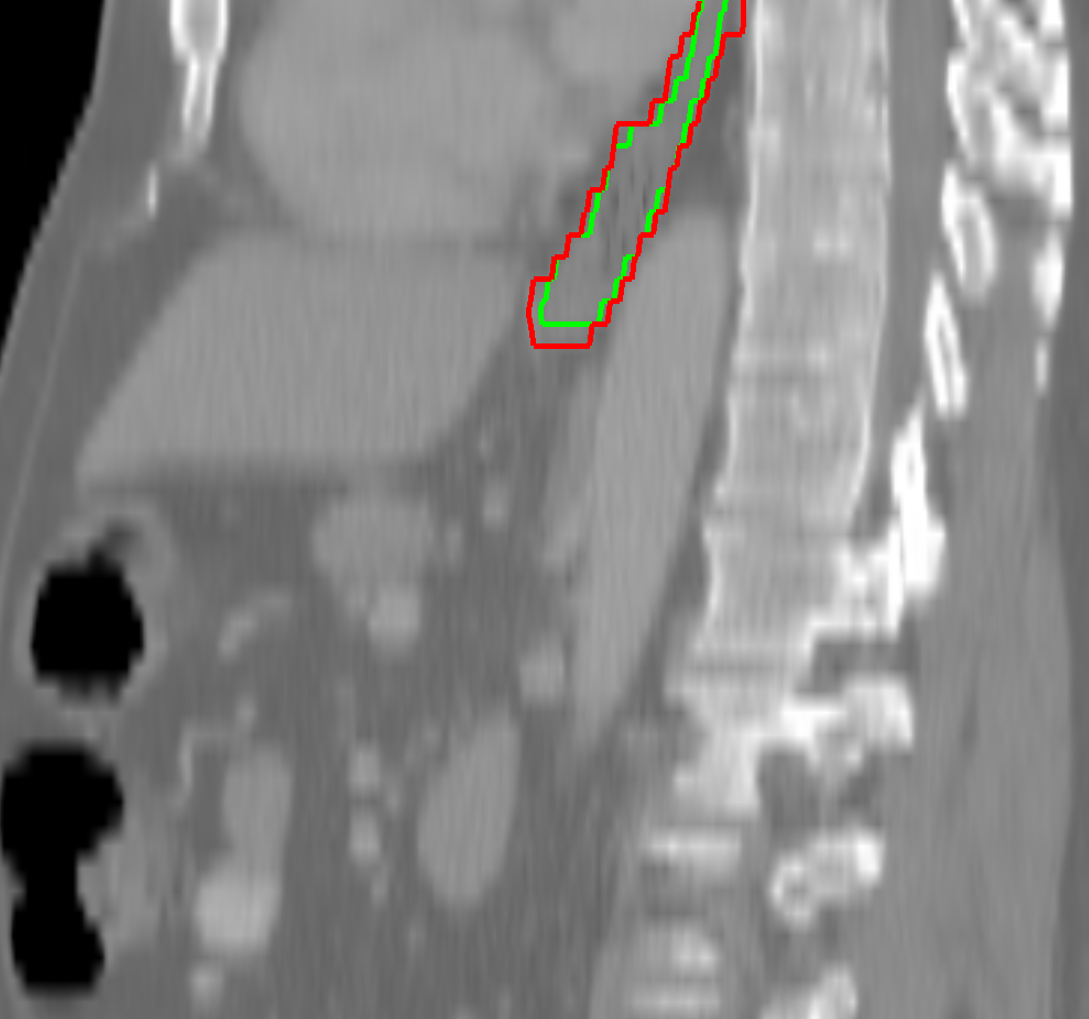

Visual results of our algorithm compared to the reference contour for 6 cases in axial and sagittal view are depicted in Fig. 5. From the sagittal views it can be observed that manual contours are not as smooth as the automatic contours, which could be due to the breathing artifacts. The use of convolutions and post-processing in 3D aids at processing information of the 3D context through several slices, which is reflected in the smoother automatic contours shown in these images. On the other hand, from the axial views we can realize that, despite of the similarity with respect to neighboring tissues, and heterogeneity of the inner region of the esophagus, our automatic system provides contours that are comparable with the reference standard.

Refer to caption a) clinical case 09 sagittal view Refer to caption b) clinical case 13 sagittal view Refer to caption c) clinical case 20 sagittal view

Refer to caption d) clinical case 09 axial view Refer to caption e) clinical case 13 axial view Refer to caption f) clinical case 20 axial view

Refer to caption g) public case 01 sagittal view Refer to caption h) public case 12 sagittal view Refer to caption i) public case 24 sagittal view

Refer to caption j) public case 01 axial view Refer to caption k) public case 12 axial view Refer to caption l) public case 24 axial view

Figure 5: Contouring results for 6 cases in different views. The green line indicates the reference standard, the red line depicts the contour generated by the proposed algorithm.